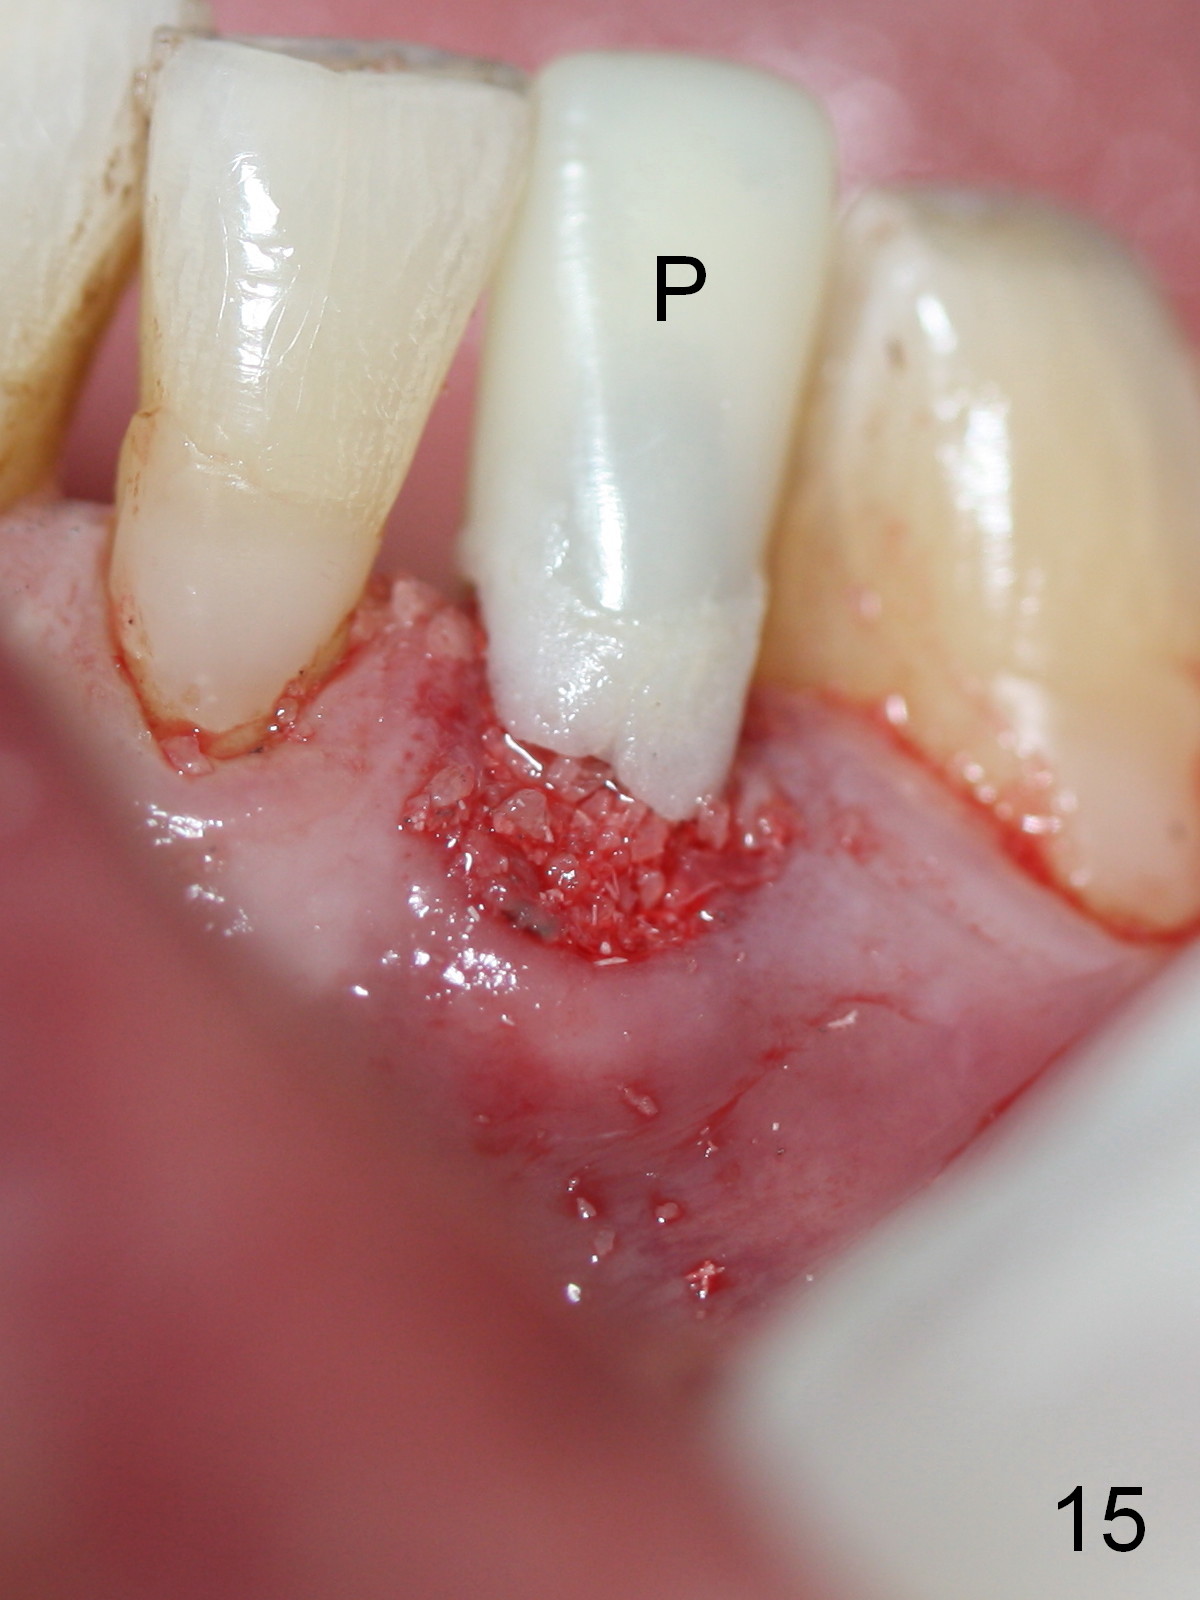

A 74-year-old man has several missing teeth (Fig.1).  His 1st goal is to replace the lower left lateral incisor (Fig.2).  The residual root has an apical lesion (Fig.3 *).  To describe intraop findings, a CT image of a different patient is used (Fig.4 coronal section; B: buccal; L: lingual).  After extraction, the buccal plate is found to be thin and low (Fig.5 arrowheads).  A 1.5 mm pilot drill (Fig.6 red line) is used to initiate osteotomy in the lingual plate of the socket.  Once the drill penetrates the lingual plate, the trajectory changes and the depth is 17 mm from the gingival margin (Fig.7).  A PA is taken (Fig.8); it appears that the osteotomy can be extended more apically.  When the pilot drill extends to 20 mm, there is sudden empty feeling.  The lingual plate has perforated (Fig.9).  A new osteotomy is established buccally (Fig.10 pink).  To avoid buccal plate perforation, especially in the buccal undercut area (>), the coronal end of the drill has to be tilted buccally (<--).  An angled abutment (3x20 mm, 15°) is placed (Fig.11,12).  The abutment is modified (Fig.13,14) to accommodate an immediate provisional (Fig.15,16 P).  Perio dressing is to be applied to prevent the bone graft from getting dislodged buccally (Fig.15).  The dressing is in place 7 days postop (Fig.17).

Five months postop, the peri-implant space reduces (Fig.18).  A keratinized band forms buccal to the implant (Fig.19 *).  The provisional dislodges probably due to the buccal placement (Fig.20).